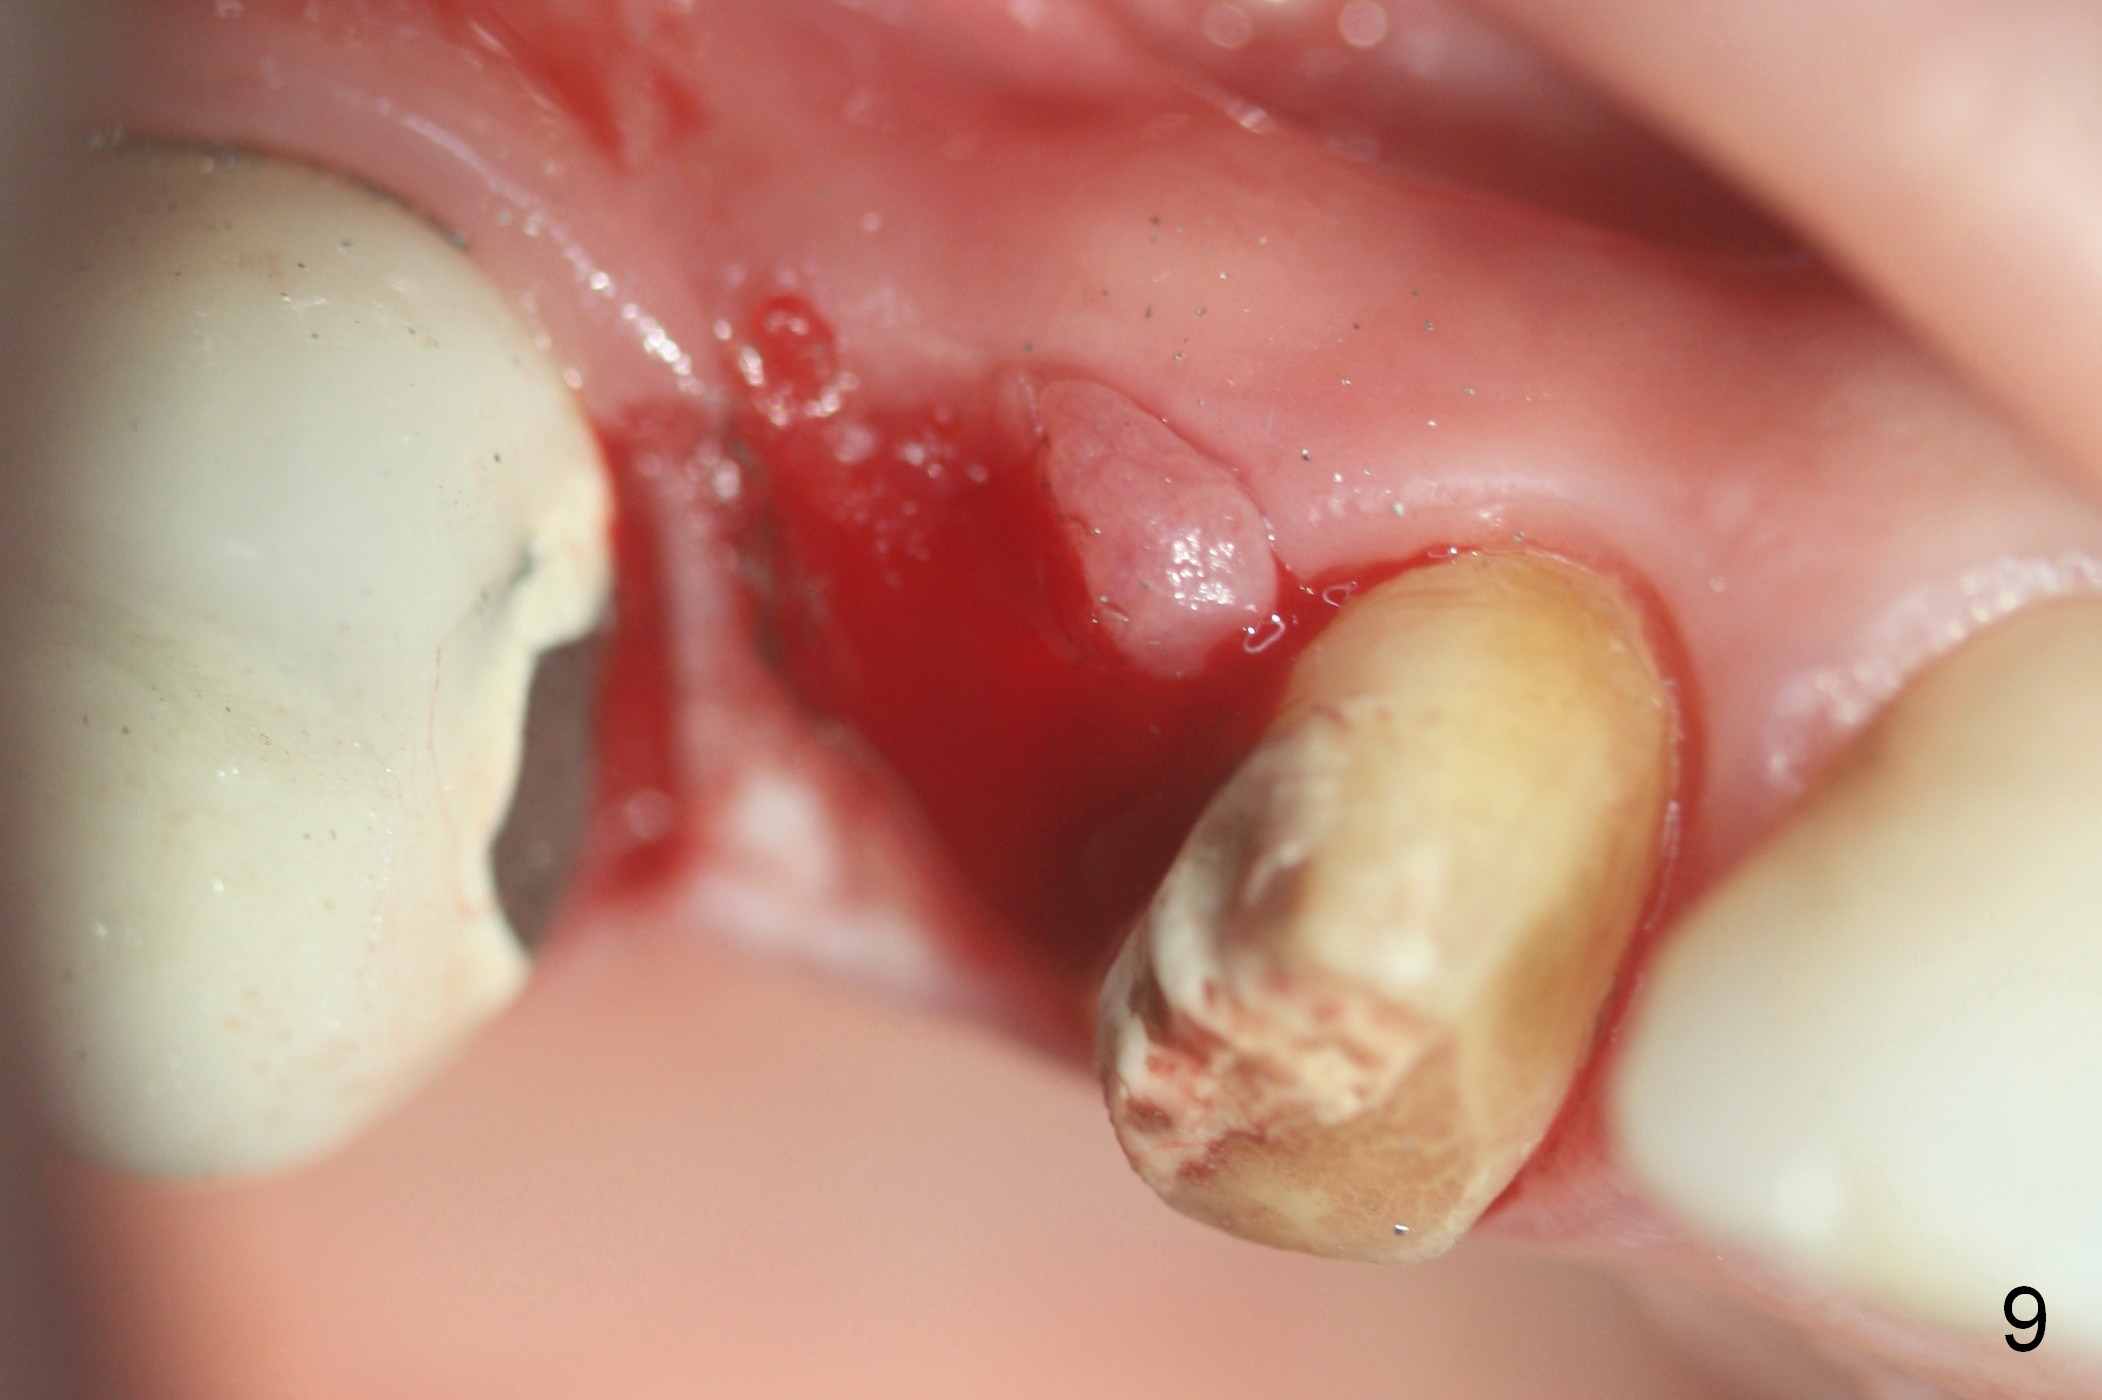

Ms. Li, a 34-year-old lady, had the upper right fixed partial denture made by an unlicensed dentist in California 10 years ago (Fig.1: #3-5). The gingival margin palatal to the retainers is erythematous (Fig.1 arrows). The patient's chief complaint is gum bleeding. The retainer at #3 is over-contoured buccopalatally (Fig.1, as compared to #14 in Fig.2), while the one at #5 is over-contoured buccopalatally and mesiodistally (compare to #12 in Fig.2). Panoramic X-ray (Fig.3), bitewing (Fig.4) and periapical film (Fig.5) all confirm that the bridge is over-contoured and that the retainers #3 and 5 have open margin (Fig.4 arrowheads). To improve oral hygiene and save the abutment teeth #3 and 5, it is in the patient's best interest to remove the bridge, place an implant at #4 and fabricate single-unit crowns at #3 and 5. Three to four months later, pyogenic granuloma develops between #4 and 5 (Fig.6 *) with generalized gingival erythema apically. The pontic at #4 and the retainer at #5 are to be removed first. An implant will be placed at #4 (Fig.7) with conjoined provisional at #4 and 5. The initial depth of osteotomy is 13 mm with Sinus Master Kit.

Eleven days later when the patient returns for bridge sectioning and implant placement, the pontic infection extends distally (Fig.8 <). When the bridge is sectioned, the pontic mucosa appears unsuitable for implant surgery (Fig.9). The patient is discharged after fabrication of a provisional at #5. She is rescheduled for implant placement 17 days later. IBS implant is to be placed because of its dual system. If the bone is soft, go to the bone expansion route. Otherwise, choose the traditional method: drilling.